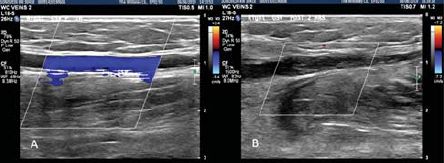

3. ábra.

Színes duplex áramlási kép mutatja a refluxot az elégtelen vena saphena magnában

(A) majd a véna elzáródását Sonovein HIFU kezelést követően

(B). (Prof. Dr. Mark Whiteley engedélyével)

Az elvégzett kezelések száma jelenleg még alacsony, de az már látszik, hogy a technológiai működik és az élmény a páciensen számára elfogadható. A kezeléseket követő duplex ultrahang kontroll vizsgálatok alapján már az is elmondható, hogy az eredmények rövid távon legalább annyira jók, mint az endovénás módszerekkel. Miután új eszközről van szó, az egyelőre jelentős méretű, drága és a kezelés nagy vénatörzseken hosszú ideig tart. Egyelőre még nem áll rendelkezésre nagyszámú adat arról, milyen betegek és mely erek kezelésében optimális a módszer és melyik betegcsoport esetében nem alkalmas, bár ebben az évtizedes endovénás tapasztalat sokat segít (3-4. ábra).